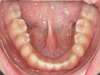

Encombrement aux deux arcades.Traitement par gouttières.

Avant

Après